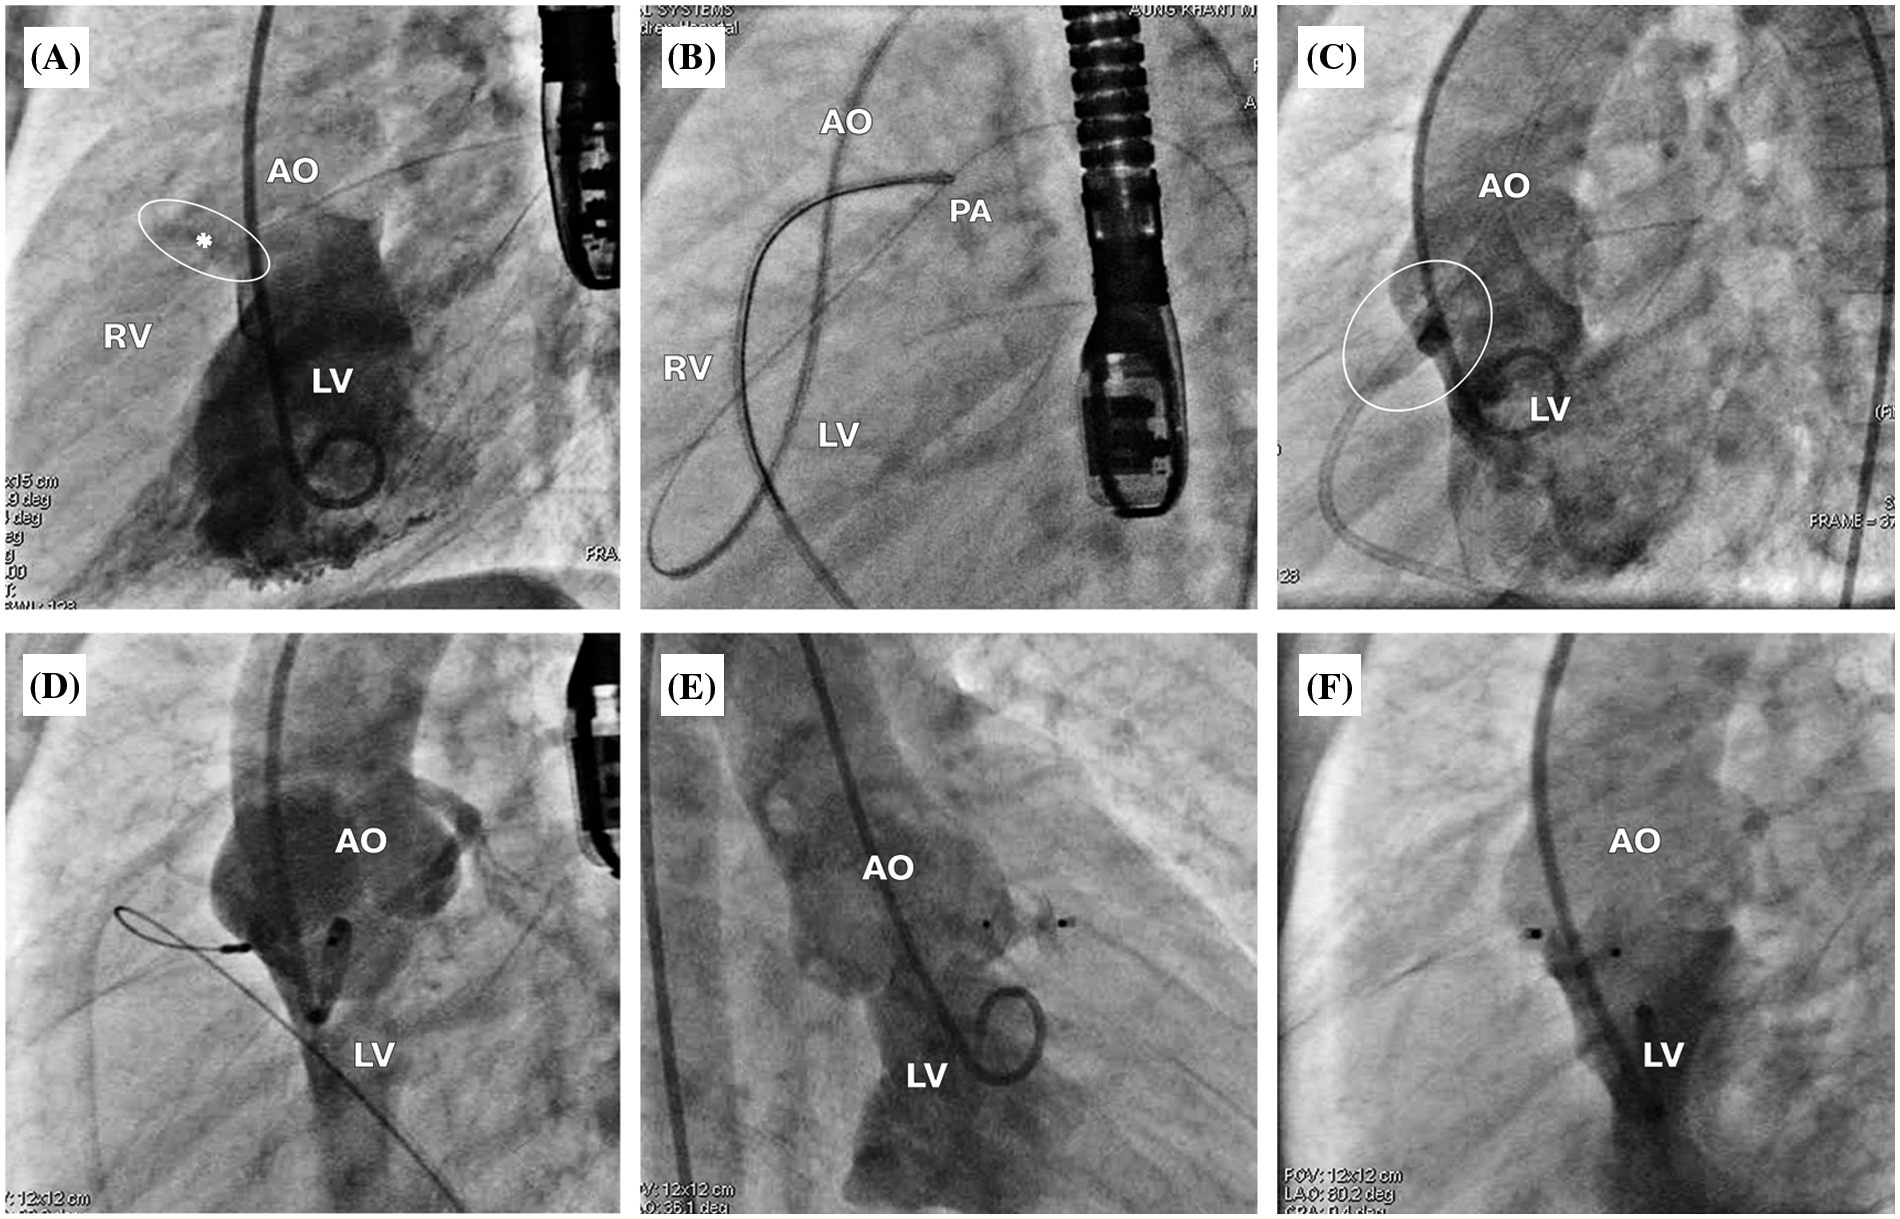

For antegrade approach (Figs. 2 and 3), the VSD was crossed from the LV using cut pigtail catheter (180°) introducing over the 0.035-inch J-Tip GLIDEWIRE® (Terumo, Tokyo, Japan) at 260 cm. The tip of cut pigtail was pointed anteriorly to ease crossing the defect. After placing the guidewire at the main pulmonary artery, it was snared via the femoral venous catheter to create the arterio-venous (AV) circuit. The 5–7 Fr delivery sheath was advanced from the femoral vein through the circuit placed at the descending aorta. VSD and degree of shunting were reassessed using repeat LV angiogram. Different occlusion devices were used for transcatheter OVSD closure as follows: AMPLATZER Duct Occluder I, II (ADO I, II; Abbott Medical, MN, USA), AMPLATZER Piccolo Occluder (APO; Abbott Medical, MN, USA), KONAR-MFTM Occluder (MFO; Lifetech Scientific, Shenzhen, China)], Nit-Occlud® Lê VSD coil (PFM coil; PFM Medical, Cologne, Germany). Generally, double-disc devices or the coil was selected for most OVSD, especially when the RV exit diameter was ≤5.0 mm (depending on device availability on shelf), whilst the ADO I was used for large defects (5.1–6.0 mm) with torrential flow. The selected device, which is 0.5–2 mm larger than the largest RV exit diameter, was introduced through the delivery sheath. The LV disc and part of the connecting waist were deployed in the ascending aorta. Subsequently, the whole system was steadily and gently pulled back across the aortic valve up to the device body seated inside the defect. Then, the RV disc was deployed by pushing the delivery cable.

Figure 2: Antegrade approach for OVSD closure. (A) The LV angiogram showing a contrast jet of OVSD (*) beneath the aortic valve from the LV to the RV in true lateral view. (B) Snaring the guidewire at the main pulmonary artery to create the atrioventricular loop. (C) LV angiography while the guiding catheter crosses the ventricular septum, demonstrating the true diameter of OVSD. (D) ADO II 3/4 was implanted through the antegrade approach. (E), (F) LV angiogram after releasing the device in right anterior oblique 30° and true lateral views, respectively